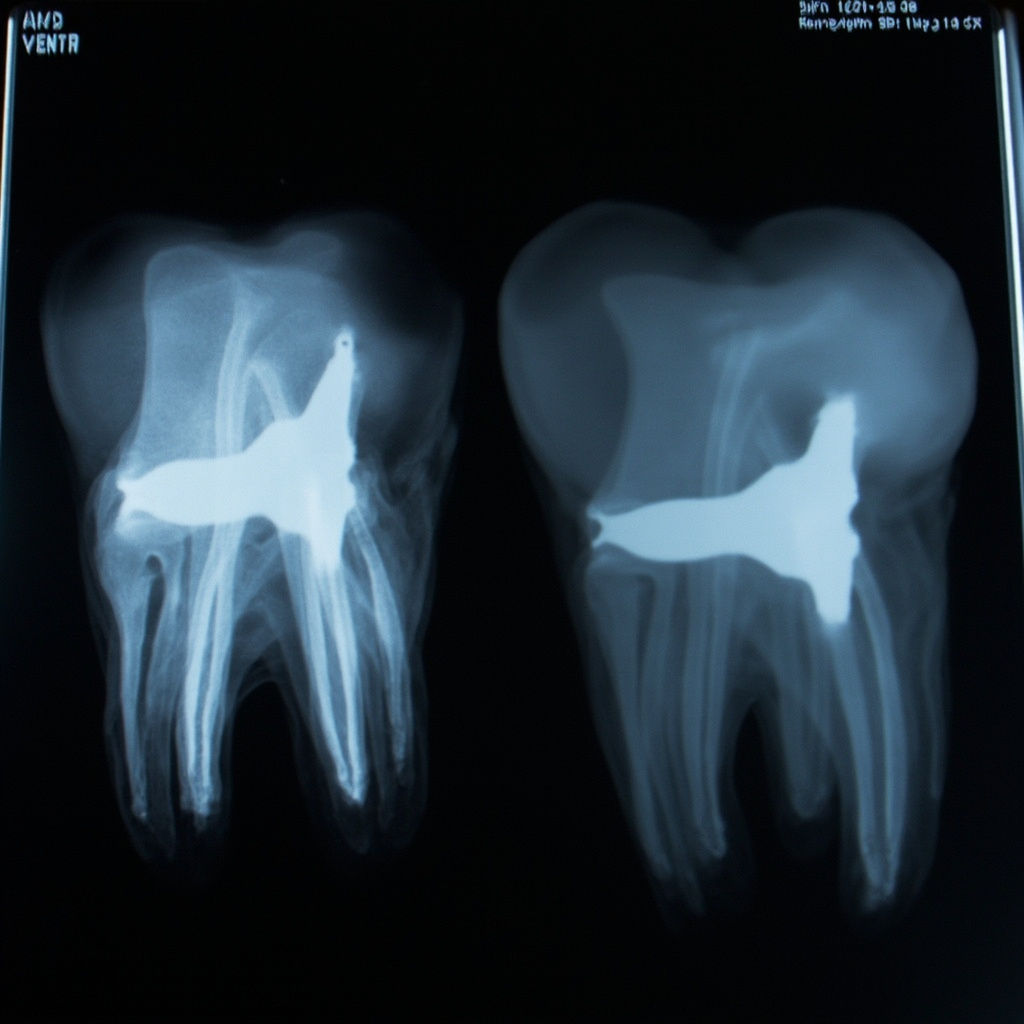

Dead pixels appear as consistently black spots in X-ray images. These pixels fail to respond to X-ray exposure and remain at zero signal regardless of the radiation intensity. Hot pixels manifest as consistently white or bright spots, remaining at maximum signal output even without X-ray exposure.

- Dark field imaging (no X-ray exposure) reveals hot pixels as bright spots

- Flat field imaging (uniform X-ray exposure) shows dead pixels as dark spots

- Visual inspection of clinical images for recurring artifacts in consistent locations